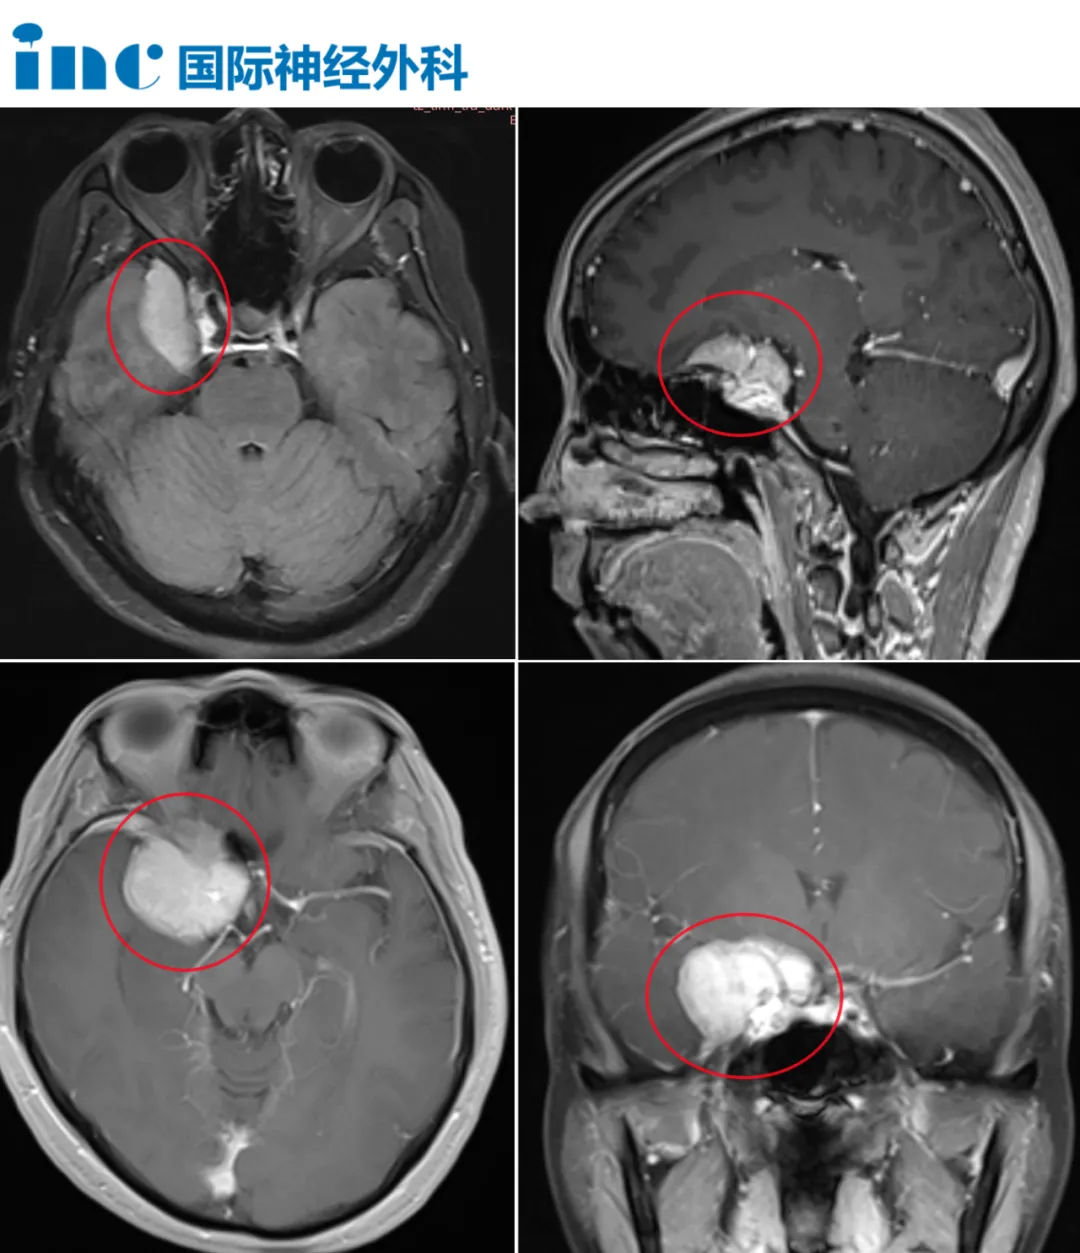

6月19日患者到医院完善CT发现颅内占位,于6月20日做增强核磁共振提示:右侧跨前中颅窝紧贴颅骨见一围绕蝶骨眶面生长不规则占位性病变,约32mmx41mmx42mm;左侧额部大脑镰左旁见小结节影,约1.0cmx1.2cm;脑干右份近桥臂见小结节异常信号影。

天降厄运,蒋女士一家遭受重击。虽然自己年近六旬,但是身体一直都只有一些小毛病,哪曾想过在自己的脑子里居然查出了三个占位,右侧的巨大脑膜瘤更是邻近海绵窦,海绵窦区神经、血管交错解剖高度复杂,涉及多个颅神经、重要脑动脉、巨大静脉丛和脑干。

福教授:右侧海绵窦脑膜瘤,左侧矢状窦旁额叶钙化脑膜瘤,脑干桥脑海绵状血管瘤。右侧海绵窦脑膜瘤应该手术治疗。左侧矢状窦旁额叶钙化脑膜瘤可以观察。脑干桥脑海绵状血管瘤可以观察。

对于右侧海绵窦脑膜瘤,手术是一个合理的选择,因为肿瘤的体积很大,并且对颞叶和视神经系统造成了很明显的压迫效应。其他两个病变目前不需要手术,只需观察。

福教授:手术难度并不大,因为大部分肿瘤生长在海绵窦外部,海绵窦内部没有多少肿瘤。我认为颈内动脉和血管都在脑沟的血管槽里,并没有完全被肿瘤包裹。我不认为颈内动脉生长在肿瘤上方。所以这是一个可以直接手术的病例。对于这个手术我并不担心。